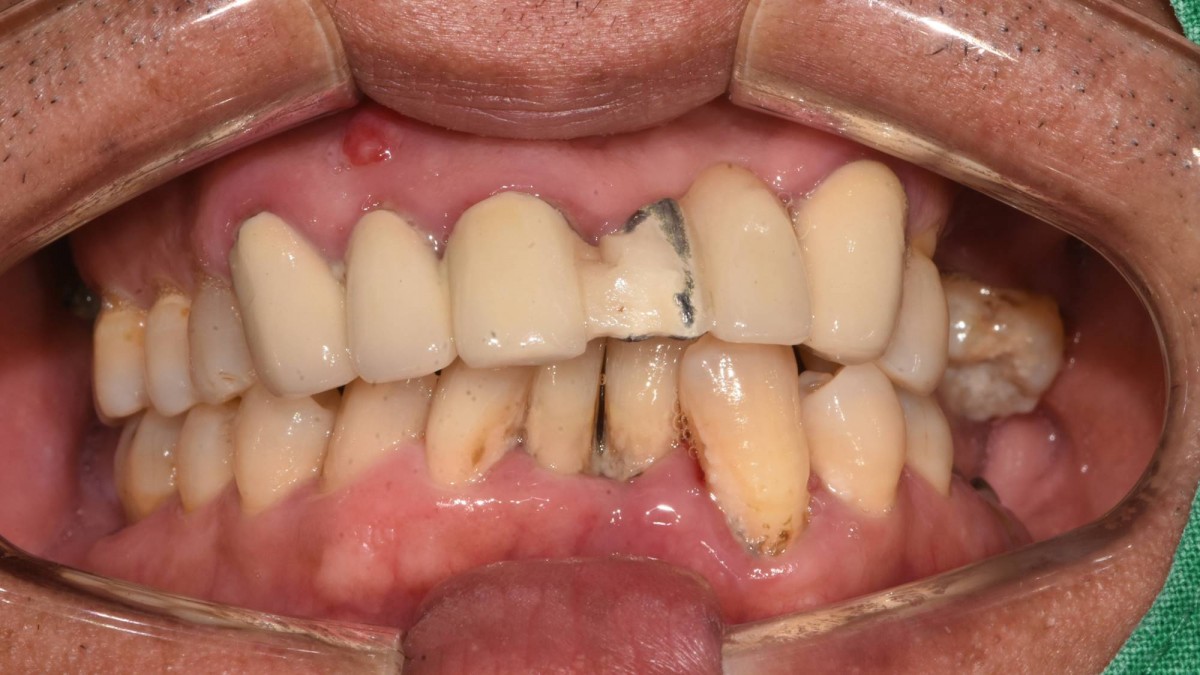

In the anterior maxilla, implant-supported fixed partial denture.

<GCpbc> A 58-year-old male is a patient undergoing implant installation in various parts. The old Br of the anterior maxilla has fallen

off and it is no longer possible to maintain it even temporarily, so a

treatment plan for the anterior teeth was made.